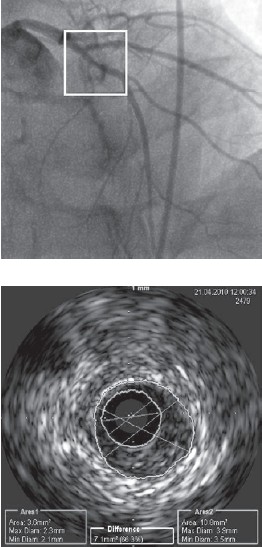

У 2 пациентов ангиографически незначимые стенозы по данным ВСУЗИ имели площадь просвета артерии менее 4 мм2 (рис. 2). Этим больным была проведена успешная ангиопластика с имплантаций стентов в пораженные участки. В течение года наблюдения сохранялся хороший клинический эффект.

Рисунок 2. Пример несоответствия данных КГ и ВСУЗИ.

По данным коронарографии, сужение передней нисходящей артерии составляет 40%, по данным ВСУЗИ, минимальная площадь внутреннего просвета артерии в этом участке 3,6 мм 2, что является гемодинамически значимым стенозом и обусловливает необходимость эндоваскулярного вмешательства.